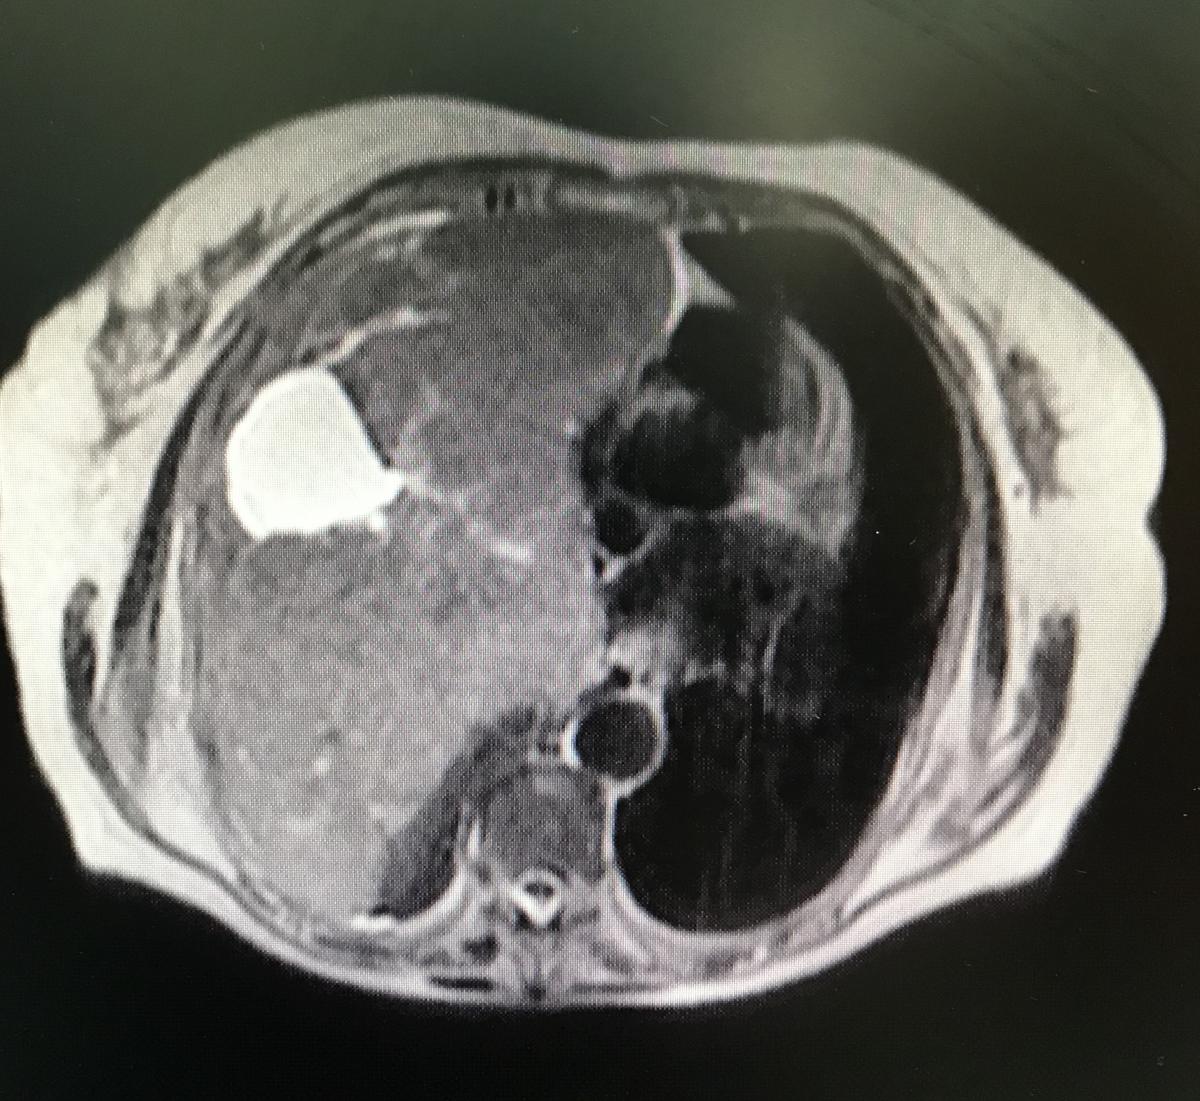

Figure 2. Magnetic resonance, axial section, T2, where the tumor is observed, with cystic areas inside, which compresses without infiltrating adjacent tissues.

Puncion biopsy was performed with trucut. The Pathological Anatomy report is: fusocellular tumor, DC 34 negative, ASMA positive, S 100 negative, NSE negative, Ki 67 2% suggesting low grade leiomyosarcoma as a diagnosis. Magnetic resonance imaging was performed to visualize the presence of infiltration, mainly of large vessels, and studies for distant disease, without finding images compatible with metastasis (figures 2 and 3).